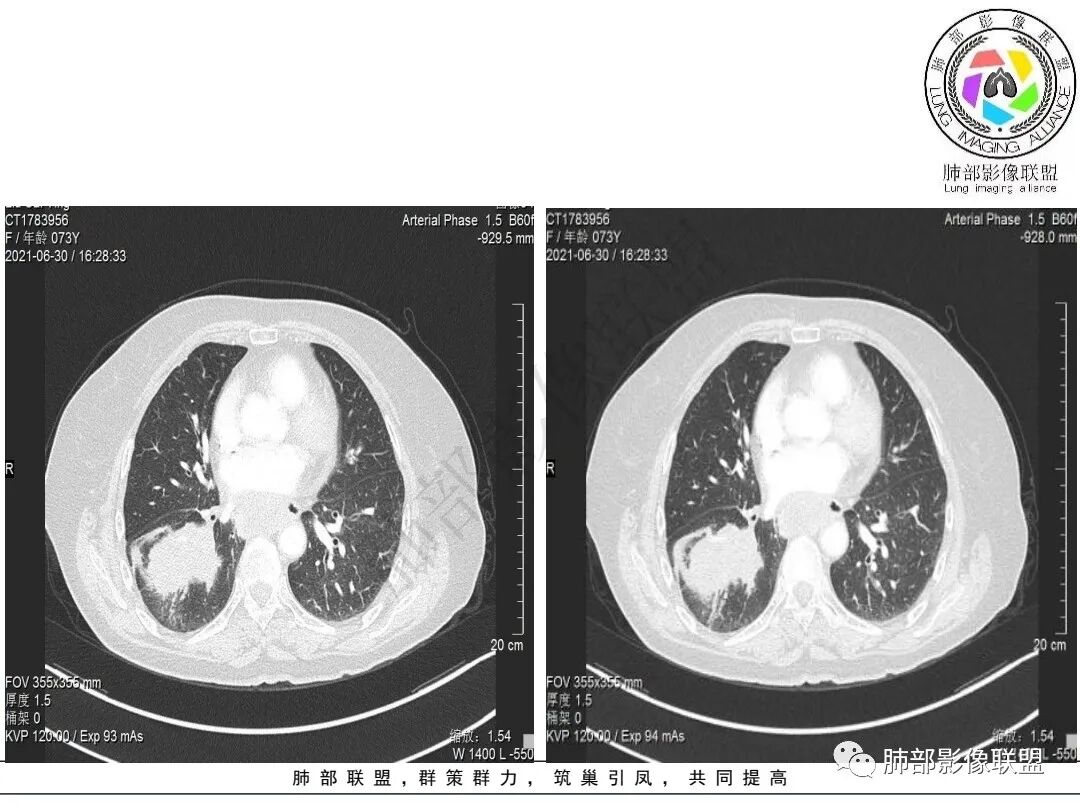

2.右肺下叶不规则实性密度块影,占据外后基底段及背段较大范围,可见轻度分叶、毛刺及棘状突起,未见明显胸膜牵拉及凹陷。

3.右肺下叶支气管轻度狭窄,病灶内见部分充气支气管征,外后基底段不能连续跟踪。

轻度不均匀强化,病灶内小血管显示不满意,未见明确坏死区。

4.右肺门及纵隔见多处增大淋巴结,不均匀环形强化,后下纵隔(隆突下)肿大淋巴结十分显眼!

1)女性不吸烟患者,病灶虽强化不显著,但未见大范围坏死或空洞,肺鳞癌的可能性较小。

2)块影收缩乏力,强化不显著,不是典型的肺腺癌影像学表现。

3)病灶强化不显著,支气管相关,纵隔淋巴结肿大明显,小细胞癌的可能性是比较大的。黄勇老师曾统计后下纵隔(隆突下)显著肿大淋巴结,小细胞癌占比相当高,临床实践也是如此。

4)应当排除的还有粘液表皮样癌、腺样囊性癌、淋巴上皮瘤样爱、混合癌等等……